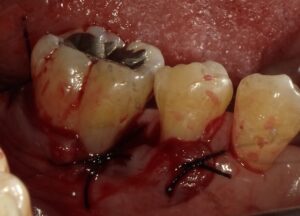

画像の様なイメージになります。針金を使いませんので

見た目がよくまた維持力も大きくとても良好な義歯となります。